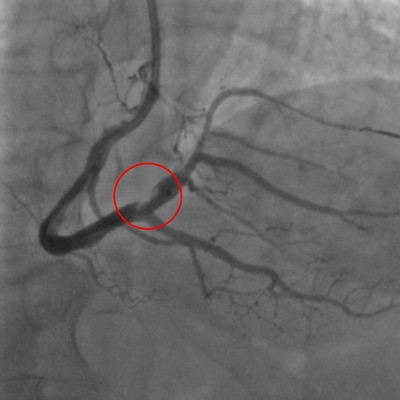

左圖:抽出血栓後使原右冠狀動脈原發病灶清楚現形,得以精準置放支架,完成血管的暢通。

六十七歲萬先生是在凌晨一點左右感到胸悶不適,上午九點經救護車送往急診室,初步檢查確定為急性下壁心肌梗塞後,立刻由「救心小組」接手,送心導管室,由心功能檢查室主任劉維新醫師與團隊緊急進行心導管治療。劉維新主任表示,最理想的狀況是清除血栓後再處置原發病灶,但在萬先生的右冠狀動脈及後降支、後側支構成的三岔路口有大範圍血栓,位置棘手加上血栓過多,在置放節律器後多次以人工抽吸方式清除血栓卻成效甚微,且出現心因性休克。

急救過程,由王惠生醫師將血栓抽乾淨,能清楚看見右冠狀動脈原發病灶,即血管壁上的斑塊,再由劉維新醫師精準置放支架,完成血管的暢通。萬先生於術後三日移除葉克膜、五日後脫離呼吸器,並於術後一週自加護病房轉至普通病房,復健半個月後即出院。